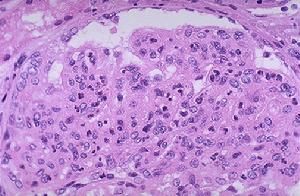

慢性腎小球腎炎病理改變與病因、病程和類型不同而異。可表現為瀰漫性或局灶節段系膜增殖膜增殖、膜性、微小病變、局灶硬化、晚期腎小球纖維化或不能定型除腎小球病變外,尚可伴有不同程度腎間質炎症及纖維化,腎間質損害加重了腎功能損害。晚期腎小球腎炎腎皮質變薄、腎小球毛細血管袢萎縮發展為玻璃樣變或纖維化,殘存腎小球可代償性增大腎小管萎縮等。